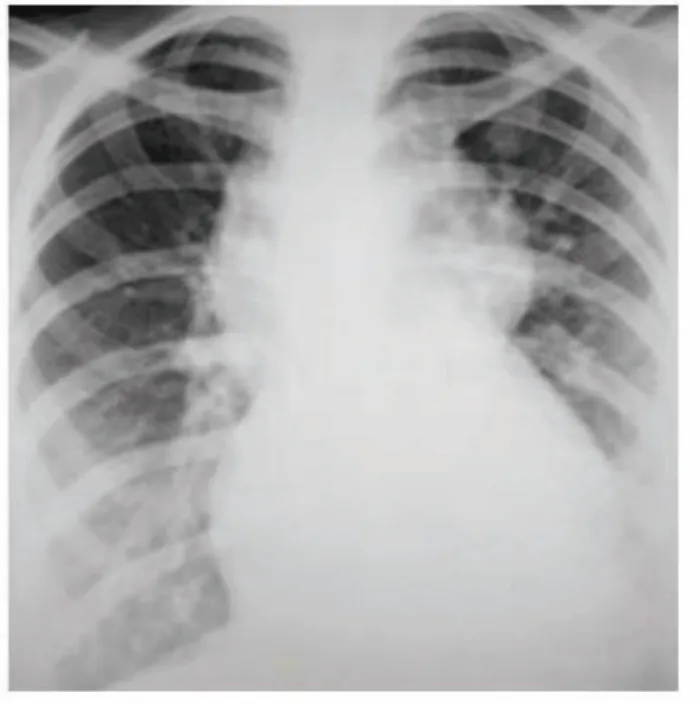

- ECG + CXR: Identify arrhythmias, cardiomegaly, pulmonary oedema